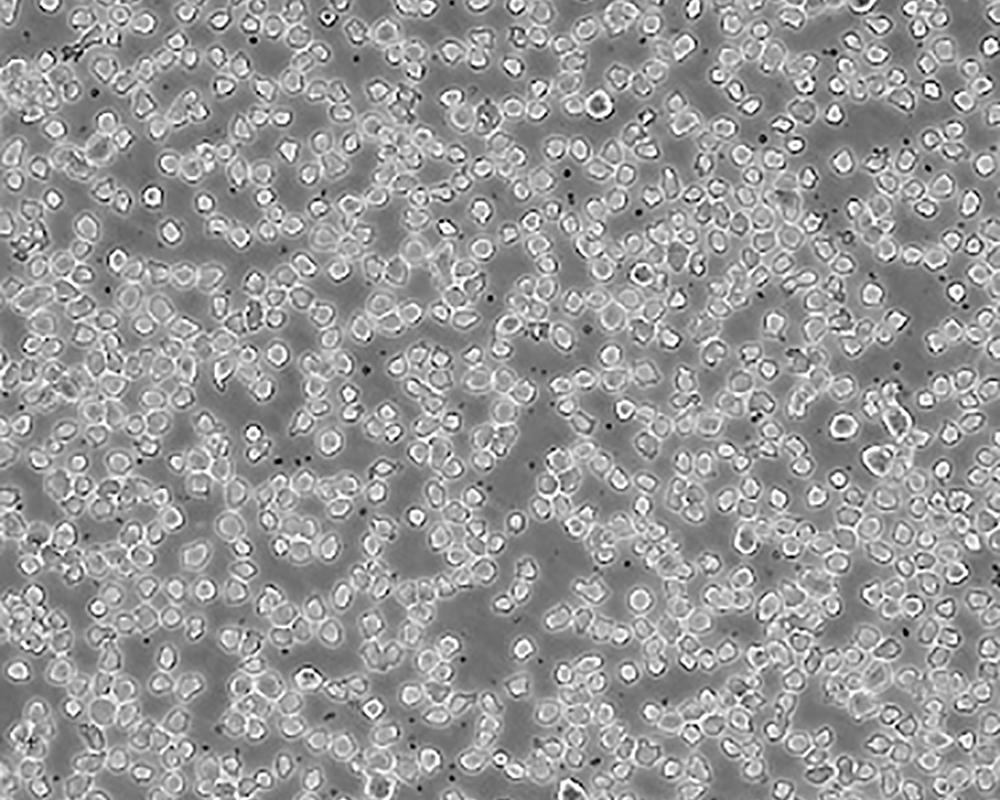

THP-1

產(chǎn)品名稱 THP-1

中文名稱 人單核細(xì)胞白血病

組織來源 急性單核細(xì)胞白血病;男性

生長(zhǎng)特性 suspension

形態(tài)特征 monocyte

細(xì)胞描述 該細(xì)胞從一名1歲的患有急性單核細(xì)胞性白血病的男孩的外周血中分離建立。該細(xì)胞可以吞噬乳膠顆粒和激活的紅細(xì)胞,細(xì)胞膜和胞漿內(nèi)均沒有免疫球蛋白,表達(dá)C3R和FcR;可受佛波酯TPA誘導(dǎo)向單核系方向分化;可作為轉(zhuǎn)染宿主。